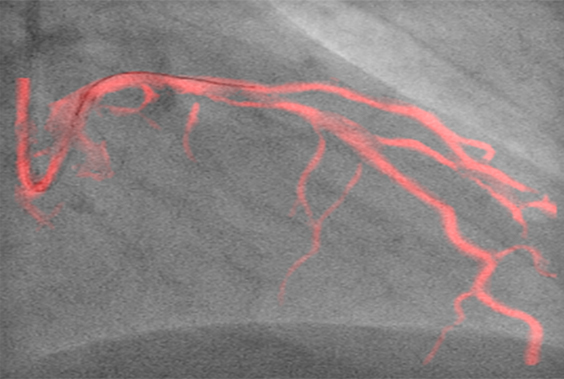

Dynamic Coronary Roadmap

Azurion(아주리온)은 최신 인터벤션 소프트웨어가 탑재되어 있어 심혈관중재시술 시 더욱 용이하게 환자를 시술할 수 있도록 해준다. 최근 도입된 다이내믹 코로너리 로드맵(Dynamic Coronary Roadmap)과 스텐트부스트 라이브 (StentBoost Live)는 복잡하고 어려운 심장 혈관 및 심장 구조 질환의 치료에 성공적인 시술을 할 수 있도록 도와준다. 두 기술 모두 까다로운 심혈관중재시술 시 실시간 레퍼런스로 활용할 수 있어, 시술 시간의 단축, 방사선 피폭 및 조영제 사용량을 최소화할 수 있다.